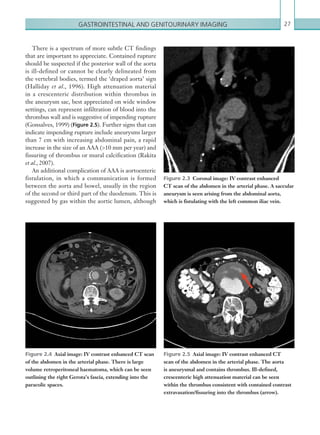

IVC, which can simulate intraluminal thrombus.

Thrombus should be suspected in the presence of a

focal filling defect in the SVC lumen, which may also

cause expansion of the lumen with localised stranding